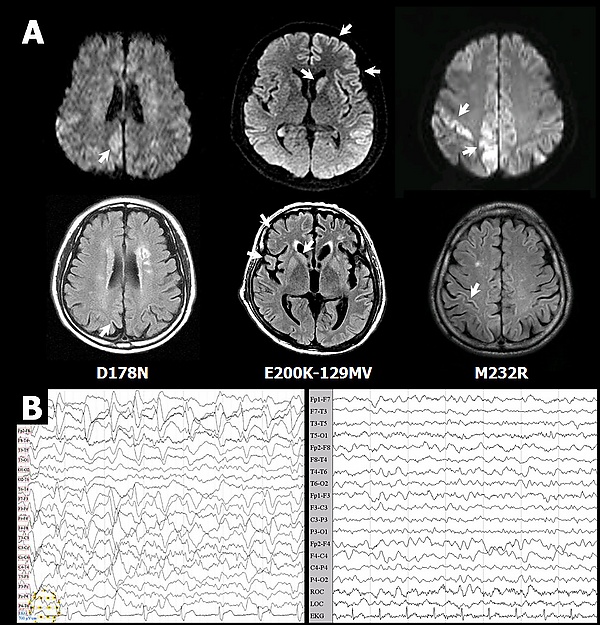

Описано более 20 мутаций гена, ассоциированных со следующими прионными заболеваниями:

- Болезнь Крейтцфельдта — Якоба (англ. Creutzfeld-Jakob disease)